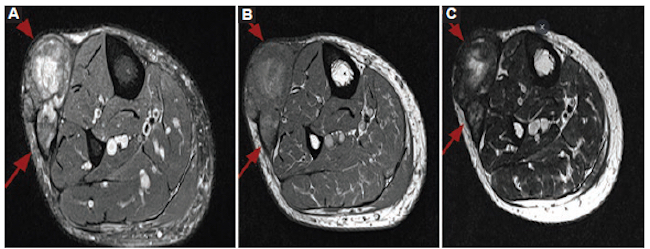

Varón de 50 años con antecedentes de diabetes que se internó por neumonía y presentó también una tumoración en la pierna derecha, de crecimiento lento, sin recordar ningún episodio traumático. La RM informó lesión de aspecto tumoral, considerando el sarcoma de partes blandas como principal diagnóstico diferencial, y se sugirió su biopsia. El resultado de la biopsia guiada por ecografía informó material fibrinoide con escasa cantidad de células. Ante la imposibilidad de descartar una neoplasia, se realizó resección quirúrgica con márgenes oncológicos (Fig. 3).

El resultado de anatomía patológica evidenció un hematoma organizado. El paciente evolucionó clínicamente estable y se le otorgó el alta hospitalaria.